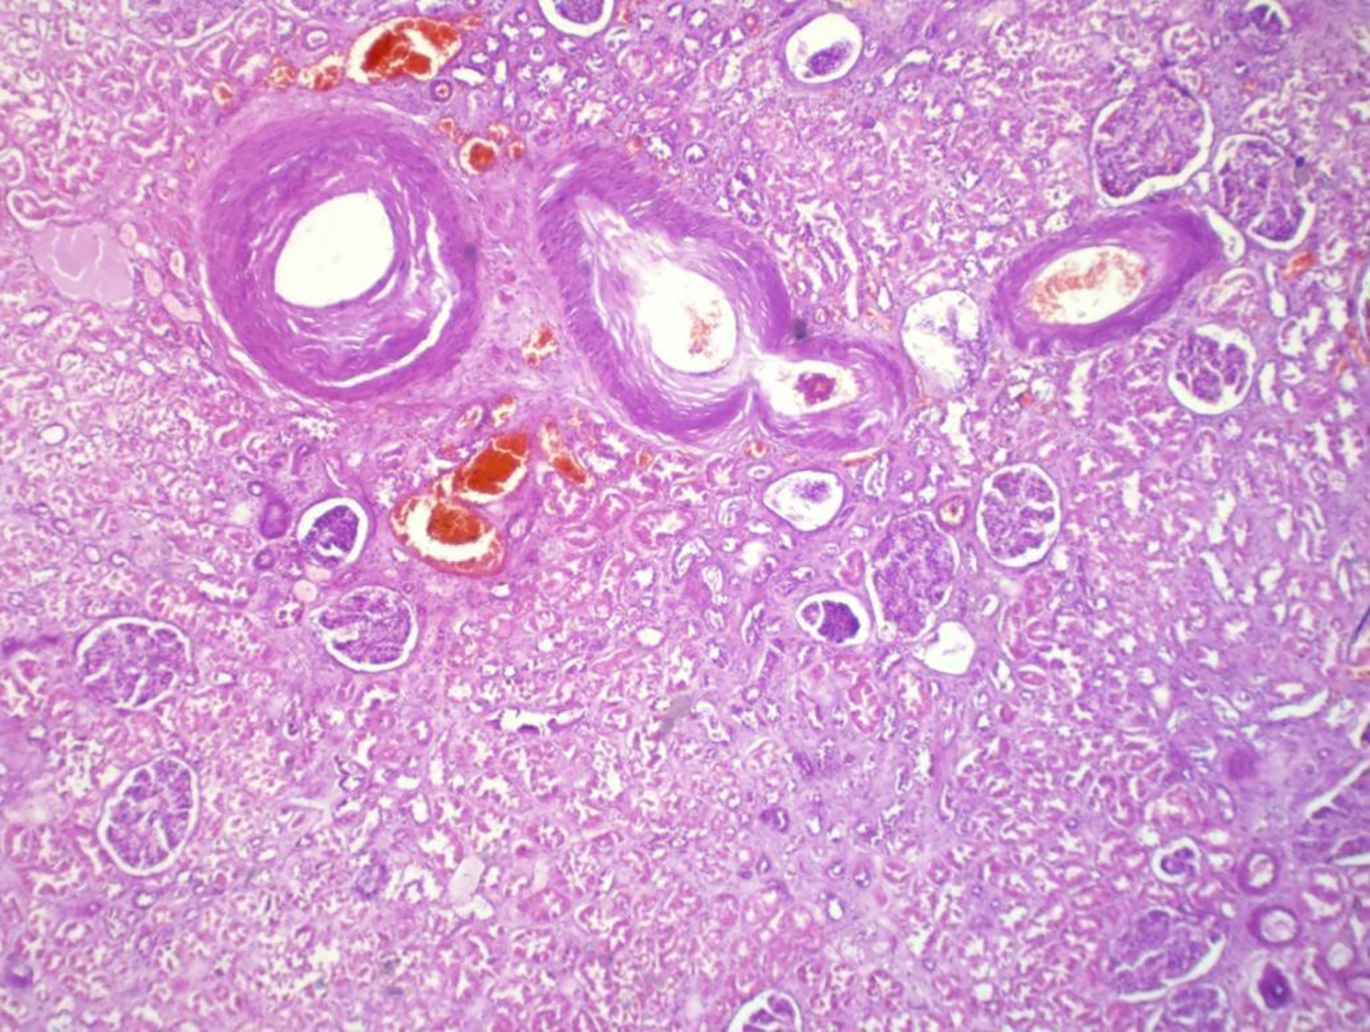

Микроскопически диабетическая нефропатия характеризуется сосудистым гиалинозом афферентных и выносящих артериол, крупными субэндотелиальными отложениями липогиалина на периферии клубочковых петель. Подобные отложения располагаются также вдоль капсулы клубочка (Шумлянского–Боумена). На поздних стадиях в ткани почки определяется сегментарный гломерулосклероз. Обнаруживаются также атрофия канальцевого эпителия, хроническое интерстициальное воспаление, фиброз и утолщение базальных мембран канальцев. При развитии тяжёлой эклампсии к явлениям хронической сосудистой патологии присоединяются изменения, носящие острый характер: коагуляционный некроз канальцевого эпителия, фибриноидный некроз сосудов микроциркуляторного русла (в том числе и капилляров клубочка), отёк и полнокровие интерстиция (рис. 4).

Рис. 4. Выраженный артериосклероз и гиалиноз сосудов почки у пациентки с тяжёлой преэклампсией на фоне сахарного диабета. Окраска гематоксилином и эозином; ×40.

Fig. 4. Severe arteriosclerosis and hyalinosis of renal vessels in a patient with severe preeclampsia secondary to diabetes mellitus. Hematoxylin and eosin staining; ×40.